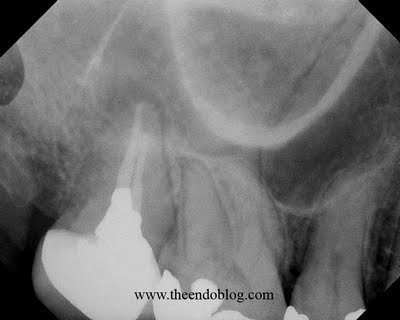

I was surprised to see a large resorptive defect on the DB root surface. This defect has destroyed most of what was once a DB root. Non-surgical retreatment of this tooth would result in perforation and extrusion of RCT material, and likely failure. It was determined that surgical treatment of this tooth would also have a poor prognosis as well. Extraction has been recommended.

Also noted was a perforation in the floor of the Mx sinus, with adjacent sinus inflammation. This tooth is also causing a sinusitis of dental origin. Removal of this tooth should help clear up some of the chronic sinus issues the patient has been experiencing.

Another example of CBCT showing what you cannot see in a traditional radiographic image. Neither of these problems were identifiable with regular imaging and were not the purpose were were taking the scan. However, identifying the root resorption and the sinus perforation had a significant impact on the diagnosis and treatment plan for this patient. The CBCT is a valuable tool for case selection which improves the rate of successful of endodontic treatment at Superstition Springs Endodontics.